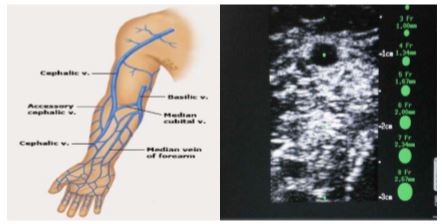

• Canalizacion venosa

• Insercion PICC (cateter COOK’s Medical)

• Insercion PICC ARROW

• Insercion de PICC bajo control ecográfico

Protocolo de inserción y mantenimiento de PICC (CHOSPAB)

Manual de acceso vascular para Enfermería.

Canalizacion PICC Arrow (II) para Enfermeria (Videoprotocolo)